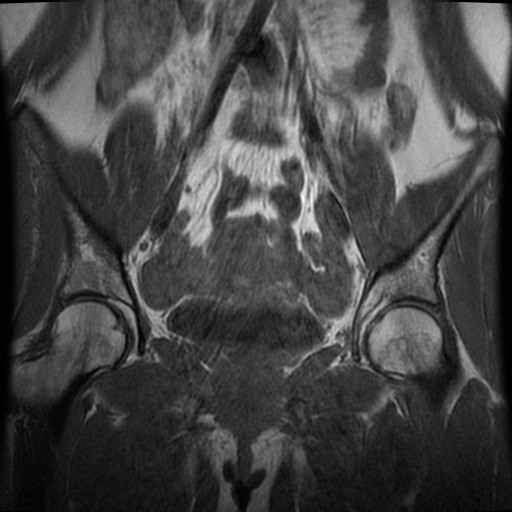

Bekken